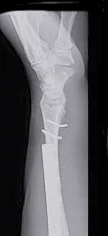

Monteggia Fracture/Dislocation

- Fracture of the proximal third of the ulna with dislocation of the head of the radius

- Dislocated head of radius missed if two joints are not included on the x-ray

- “Fracture of necessity”. Treated by:

- Open reduction and internal fixation of ulna

- Closed reduction of head of radius

- +/- fixation